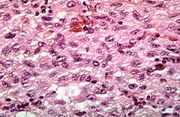

| 02:07, 21 August 2013 | IPLab7Carcinoid4.jpg (file) | 77 KB | This is a high-power photomicrograph of the surgical specimen showing the cellular morphology. The tumor cells are monotonously similar with scant, pink, granular cytoplasm and a round-to-oval stippled nucleus. As in most carcinoid tumors, there is min... | 1 | |